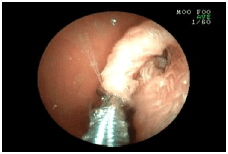

4. 胃のしこりを調べた例

![]() |

吐きを繰り返している犬の胃の中です。 ぐるりと内側を取り囲むように腫れあがっていました。(矢印) |

しこりの内容を調べるために、腫れあがった部分の一部をつまんで持ち帰ろうとしているところです。 検査の結果、このしこりは免疫のしくみで起こっている炎症だと分かりました。 |